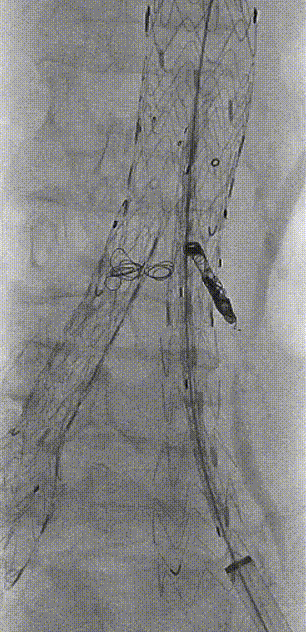

保留Amplatz导丝,于体外将260cm软泥鳅导丝置入GORE髂动脉分支型覆膜血管内支架CEB231010(23mm-10mm-100mm)中,形成牵张通道,沿GORE 20Fr鞘植入IBE主体支架,退鞘至短腿下方,于目标位置释放至短腿打开,再次退鞘至长腿远端,释放IBE主体支架长腿。

gore医疗怎么样「漫腹精论」独具匠心 推陈出新——同侧IBE支架内翻山重建髂内动脉治疗EVAR术后内漏病例报道_https://www.jmylbn.com_新闻资讯_第14张

释放IBE主体到短腿

gore医疗怎么样「漫腹精论」独具匠心 推陈出新——同侧IBE支架内翻山重建髂内动脉治疗EVAR术后内漏病例报道_https://www.jmylbn.com_新闻资讯_第15张

释放IBE主体到长腿

将20Fr鞘沿泥鳅导丝硬头端送至IBE主体支架分叉处,再导入GORE DSF1245鞘经20Fr鞘沿泥鳅导丝翻山至短腿开口。

gore医疗怎么样「漫腹精论」独具匠心 推陈出新——同侧IBE支架内翻山重建髂内动脉治疗EVAR术后内漏病例报道_https://www.jmylbn.com_新闻资讯_第16张

翻山至IBE短腿开口